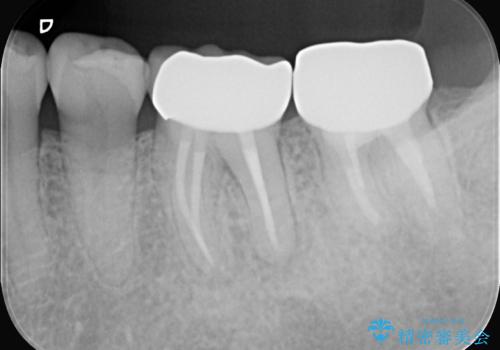

- 2日前から歯の痛みが続くという主訴でご来院されました。診察の結果、**不可逆性歯髄炎(歯の神経の重度の炎症)**と診断。レントゲンでは、歯髄腔が狭くなり、根管が石灰化している難症例であることが確認されました。患者様の大切な歯を残すため、歯科用顕微鏡を用いた精密根管治療を行うことで、狭く、見えにくい根管を正確に探し出し、治療を完了させる計画を立案しました。

今回の治療は、特に難易度の高い石灰化した根管が対象でした。まず、治療中の細菌感染を防ぐためにラバーダムを使用。次に、歯科用顕微鏡で治療部位を何十倍にも拡大しながら、狭窄した根管の入り口を探し、慎重に拡大・清掃を行いました。顕微鏡を用いることで、肉眼では不可能だった根管内部の細かい構造を確認しながら、感染源を徹底的に除去することができました。これにより、難症例の奥歯でも再発リスクを抑えた適切な処置を行うことができ、治療後に痛みは解消。大切な歯を長期間にわたり保存することができました。